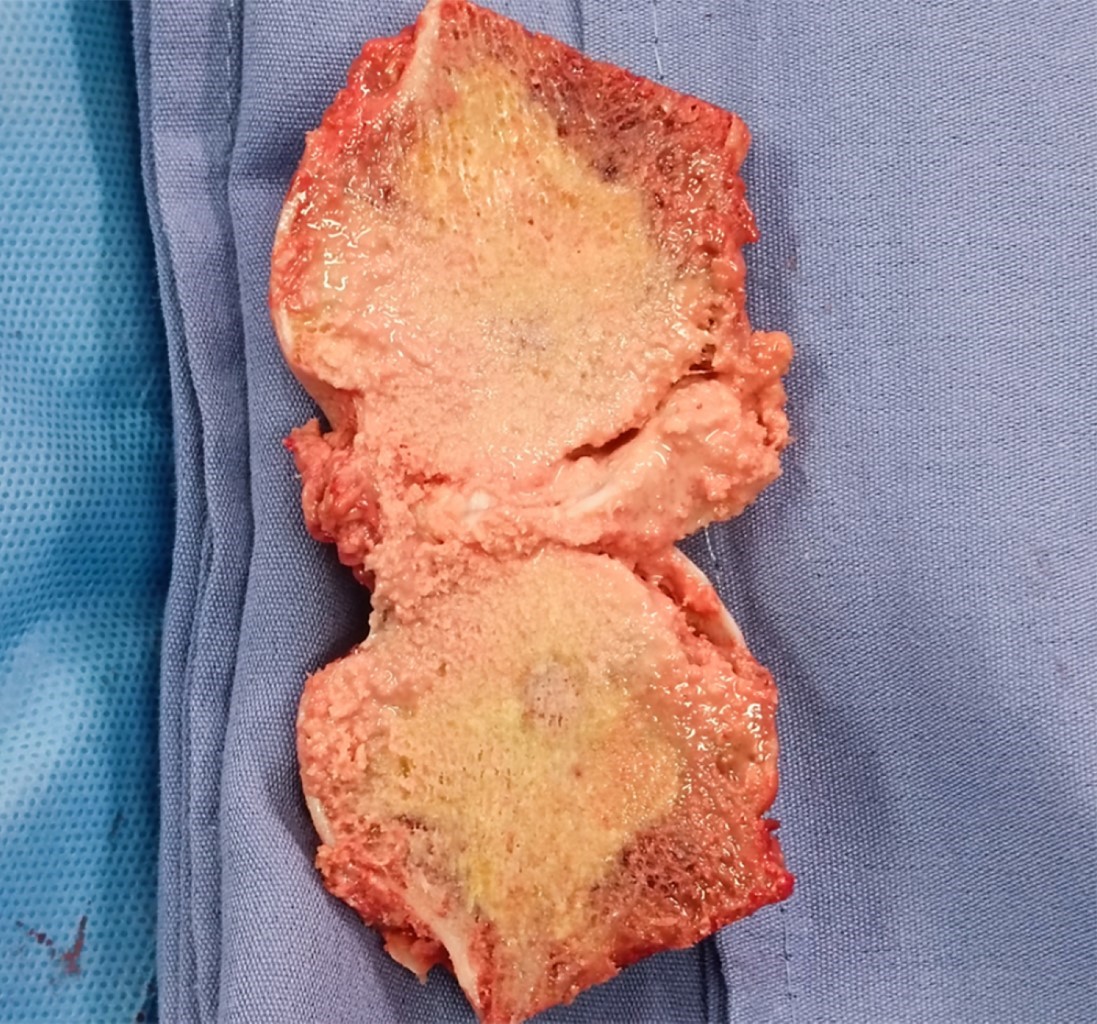

Figure 1